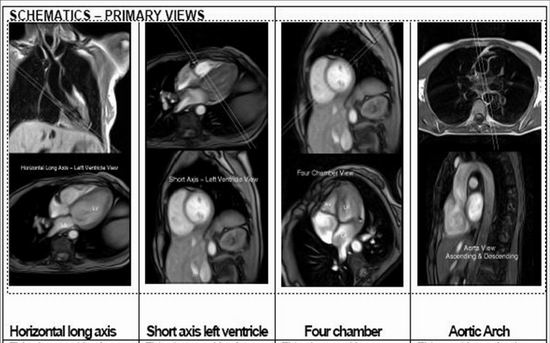

主要功能:Avanto 1.5T磁共振成系统整体提升至I-class平台,将品质图像、高工作效率、高灵活度的工作完美结合在一起,而Tim(Total imagingmatrix)则是一次革命性突破。它带来的全新的极具创造性的射频系统和矩阵线圈使之成为划时代磁共振影像技术的一大亮点,并可实现从头到脚的快速扫描,优异的图像质量能为医生和患者朋友提供强大的技术支持。